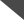

(图2:矢状位T2WI[左和中]可见T10-11和T3-4水平高信号病灶[箭],提示病变多灶性本质,横断面T2WI[右]上可见T3-T4水平右侧病灶[*]显示更清楚)